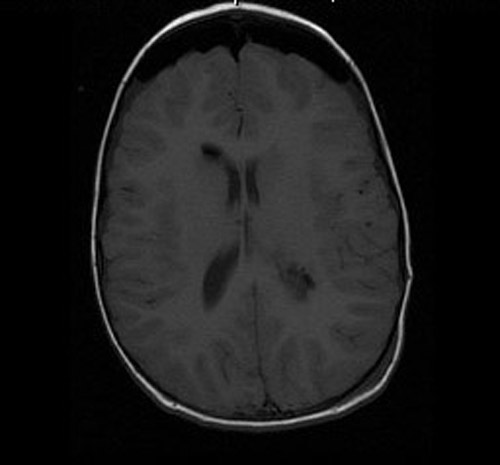

Imaging Studies:

• MRI studies demonstrate a 3.3 x 3.2 x 2.7 cm well-circumscribed mass in the left lateral ventricle. The tumor has both an exophytic part and parenchymal involvement of the underlying brain. This mass has heterogenous signal intensity on T1-weighed images and heterogeneous enhancement. On FLAIR images,  It causes a 0.5 cm midline shift to the right and mild dilatation of the right lateral ventricles. FLAIR images do not demonstrate excessive edema.

MRI FLAIR